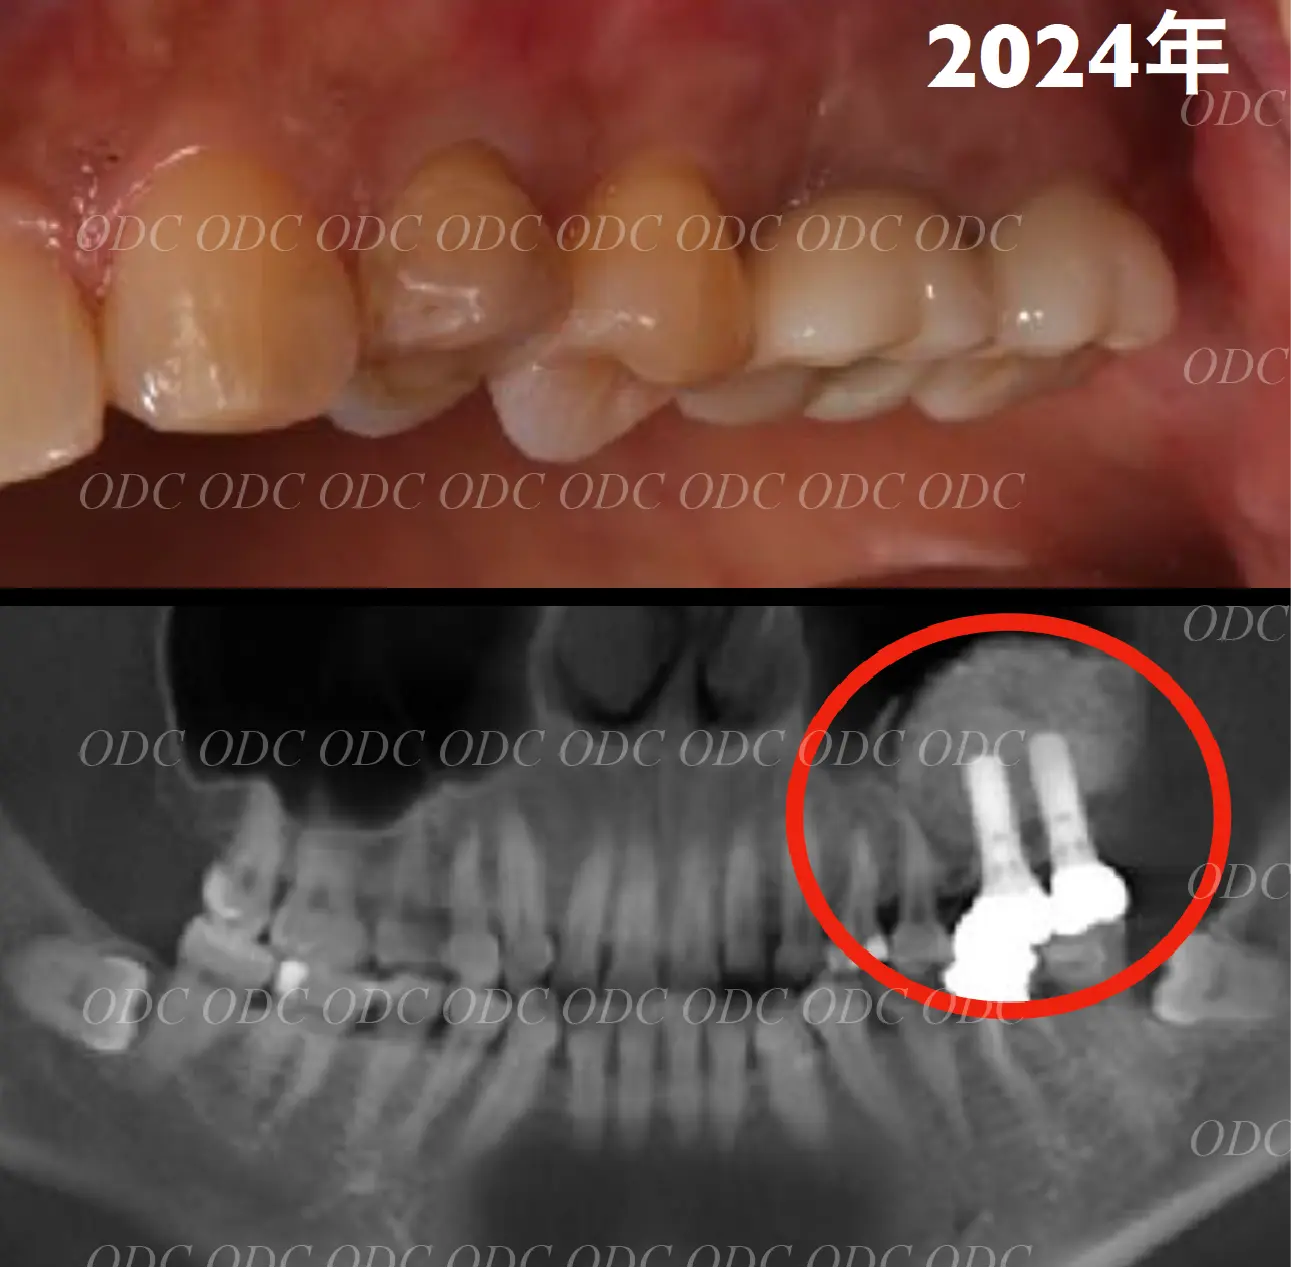

2024年、治療終了後約10年が経過いたしました。

顎関節を考慮した包括的な治療を行うことで咬合状態(噛み合わせ)は現在もとても安定した状態です。

治療終了より約11年経過しましたが現在も問題なく使用されています。

サイナスリフトした骨も全てのインプラント体も安定しております。